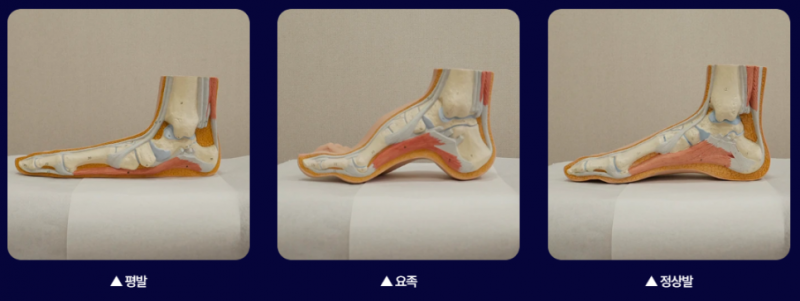

평발, 요족과 같은 발의 변형

사람의 발은 인체의 가장 밑에 있기 때문에 발이 틀어지게 되면 발목과 무릎, 고관절, 골반, 척추까지 연쇄적으로 들어지게 됩니다.

평발인 경우에는 발목이 안으로 꺾이게 되면서 무릎이 내회전 하게 되며 반대로 요족은 발목이 바깥으로 꺾이게 되면서 무릎이 외회전하게 됩니다.

평발이나 요족의 경우에는 추나나 도수, 운동을 열심히 해도 다시 회전을 유발하기 때문에 평발과 요족을 교정할 필요가 있습니다.

이때 평발과 요족을 교정하는 족부교정기 깔창을 착용하면 발목과 무릎의 회전을 예방할 수 있습니다.